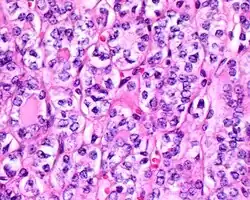

4) Must have the characteristic nuclear features of papillary thyroid carcinoma, although sometimes the features are patchy in distribution without all of the tumor showing those features. The nuclear features can be divided into three main categories:

- Nuclear size and shape: nuclear enlargement, nuclear elongation, and nuclear overlapping and crowding. Loss of nuclear polarity, with nuclei at the lumen, middle, or basal zone of the cells is also a helpful finding.

- Nuclear membrane irregularities: irregular nuclear contours, nuclear grooves and folds, "rat-bites" or demi-lune formations, and the presence of intranuclear cytoplasmic inclusions.

- Nuclear chromatin characteristics: nuclear chromatin clearing, often with condensation or margination along the nuclear membranes, resulting in accentuated nuclear margins, glassy nuclei, or fine, even delicate, powdery nuclear chromatin.

- ^ Image by Mikael Häggström, MD. Reference for findings: Rachel Jug, M.B.B.Ch., B.A.O., David Poller, M.D., Xiaoyin "Sara" Jiang, M.D. "NIFTP". Pathology Outlines.